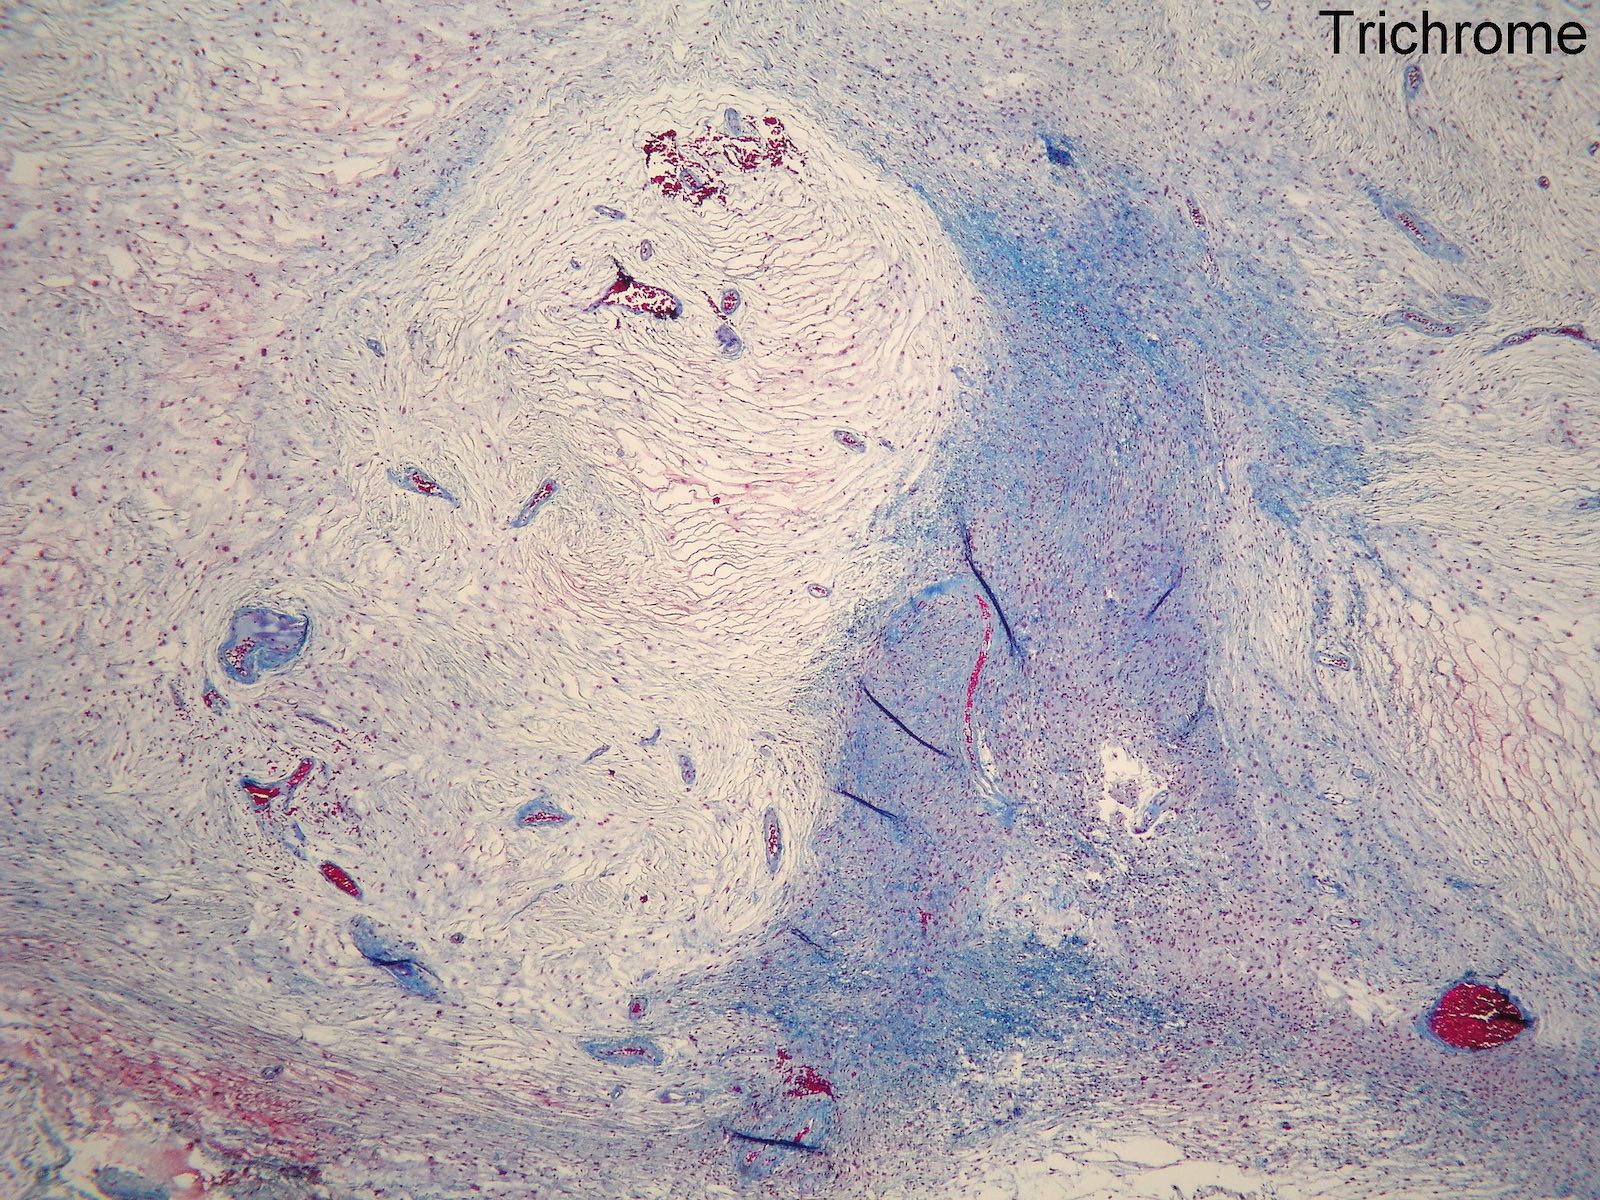

Microscopic (histologic) description

- Low to moderately cellular, bland fusiform or spindled cells with focal to diffuse whirling in heavily collagenized stroma with abrupt transition to myxoid areas

- 45% have epithelioid areas

- 40% contain poorly formed but large collagen rosettes

- Often infiltrates adjacent skeletal muscle

- Occasionally has areas of increased cellularity, atypia, necrosis or mitotic activity characteristic of intermediate to high grade sarcoma

- Recurrences may show increased cellularity and mitotic activity

Microscopic (histologic) images